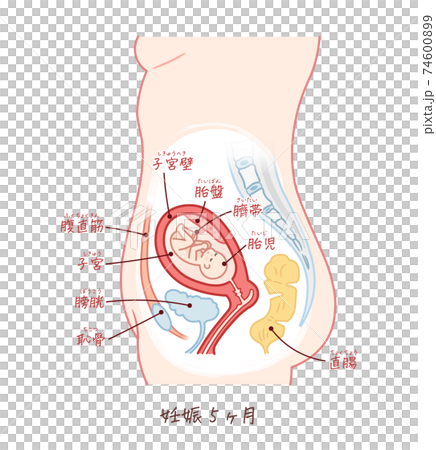

胎児の成長 妊娠5ヶ月 テキスト付きのイラスト素材74600899- PIXTA。